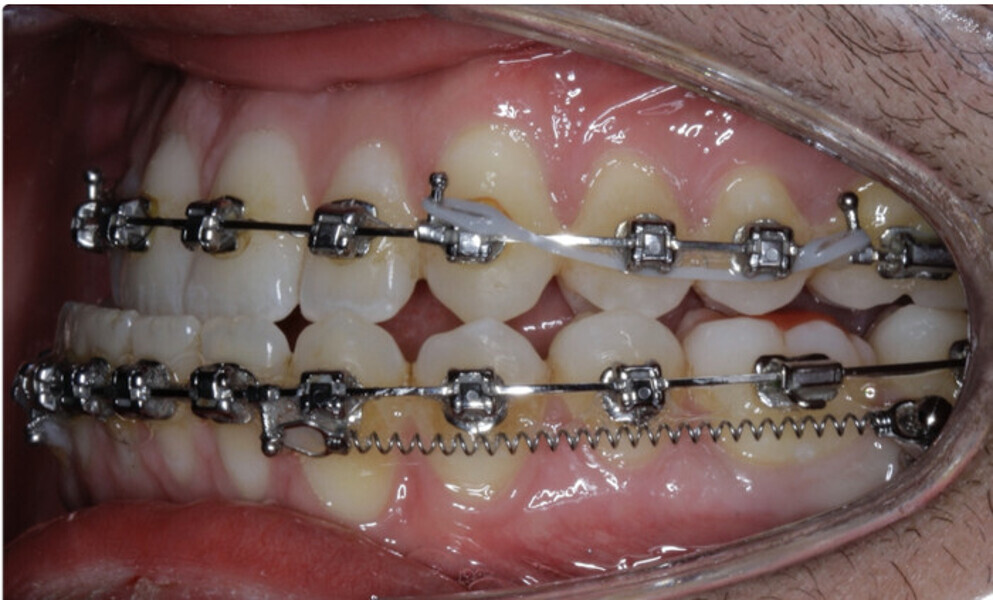

New Age orthodontics and orthopaedics with temporary anchorage devices